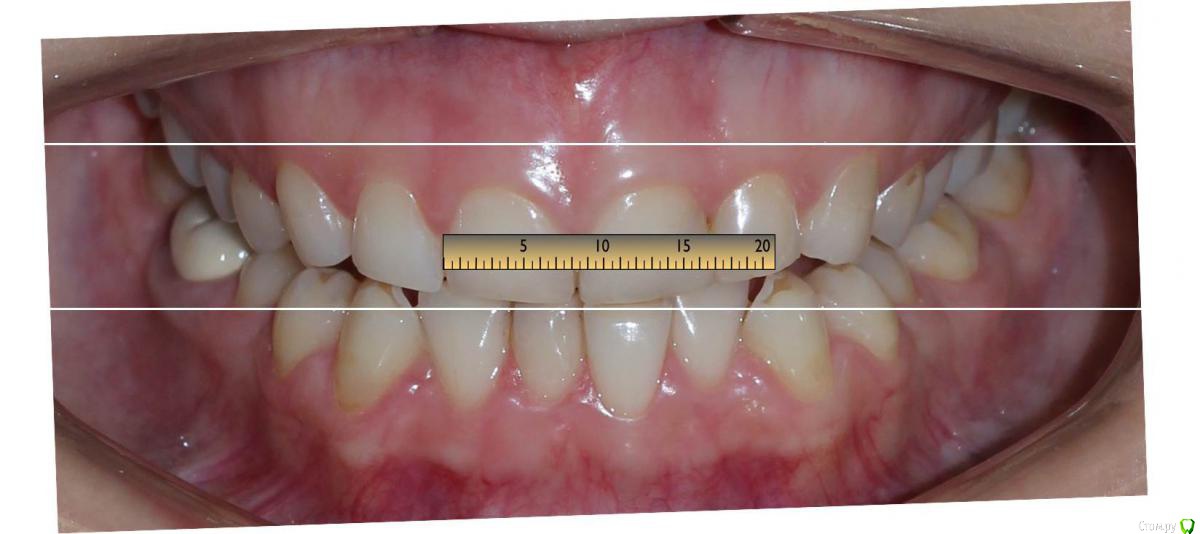

Сева северный Опубликовано 9 декабря, 2015 Поделиться Опубликовано 9 декабря, 2015 Ко мне обратилась молодая девушка, не довольная своей улыбкой. Был проведен этап планирования.... анализ улыбки ..(DSD), (wax up) и примерка (mock up)Проведенный этап...с мотивировал пациентку . 15 Ссылка на комментарий

Сева северный Опубликовано 11 декабря, 2015 Автор Поделиться Опубликовано 11 декабря, 2015 (изменено) Как вы определяете когда надо делать хир.удлинение коронки, а когда просто удлинить без хирургии. По стертым режущим краям,похоже что не было нарушения прорезывания...зондировали до ЦЭС? Или по десневой улыбке скромной решили пойти апикально?Я сделал только планирование.... Ход мысли был следующий: Длина центральных резцов 19-20 мм. Длина коронковой части зуба центрального резца 7-8 мм. Оптимальная длина 10.5. По результату пациентка с мотивирована на ортодонтию , с коррекцией gammy smile. Решение по хирургии, примем по результатам ортодонтии. Изменено 11 декабря, 2015 пользователем Сева северный 1 Ссылка на комментарий